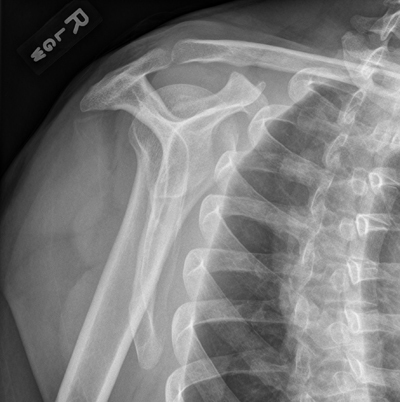

Clinical case: You are asked to review the X-rays of a 30 year old man on the Acute Medicine ward. He was admitted yesterday via A&E with generalised tonic-clonic seizure. Overnight he complained of pain in his right shoulder and the on-call doctor requested X-rays.

What do you make of the patient’s X-rays? What has happened?

What are the classic causes of posterior shoulder dislocation?